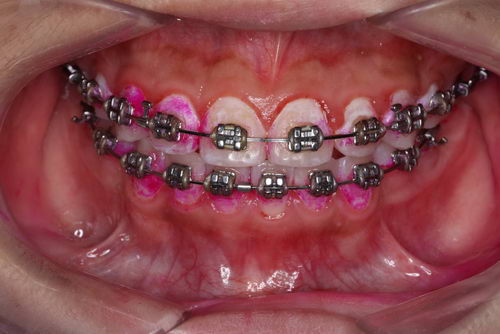

这是一位戴固定矫正装置的患者

图中牙面上的红色是通过一种染色剂标记的牙齿表面软垢的位置。第一张可以明显看到如果简单清洁,很多细节部位是清洁不到的。